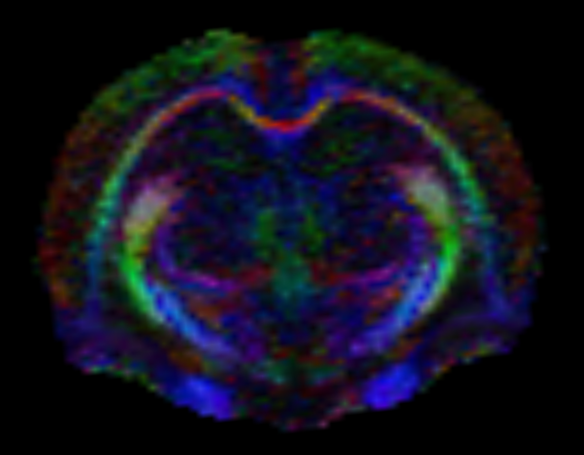

• Difüzyon tensör görüntüleme (DTI), traktografi

Dokulardaki (örneğin beyin, karaciğer) difüzyon özellikleri difüzyon ağırlıklı görüntüleme sekansları ile değerlendirilebilmektedir. Buna ek olarak, beyindeki beyaz cevher yolaklarının fraksiyonel anizotropi (FA) gibi ayrıntılı özelliklerini değerlendirmeye ve traktografisine olanak tanıyan difüzyon tensor görüntüleme yapılabilmektedir.